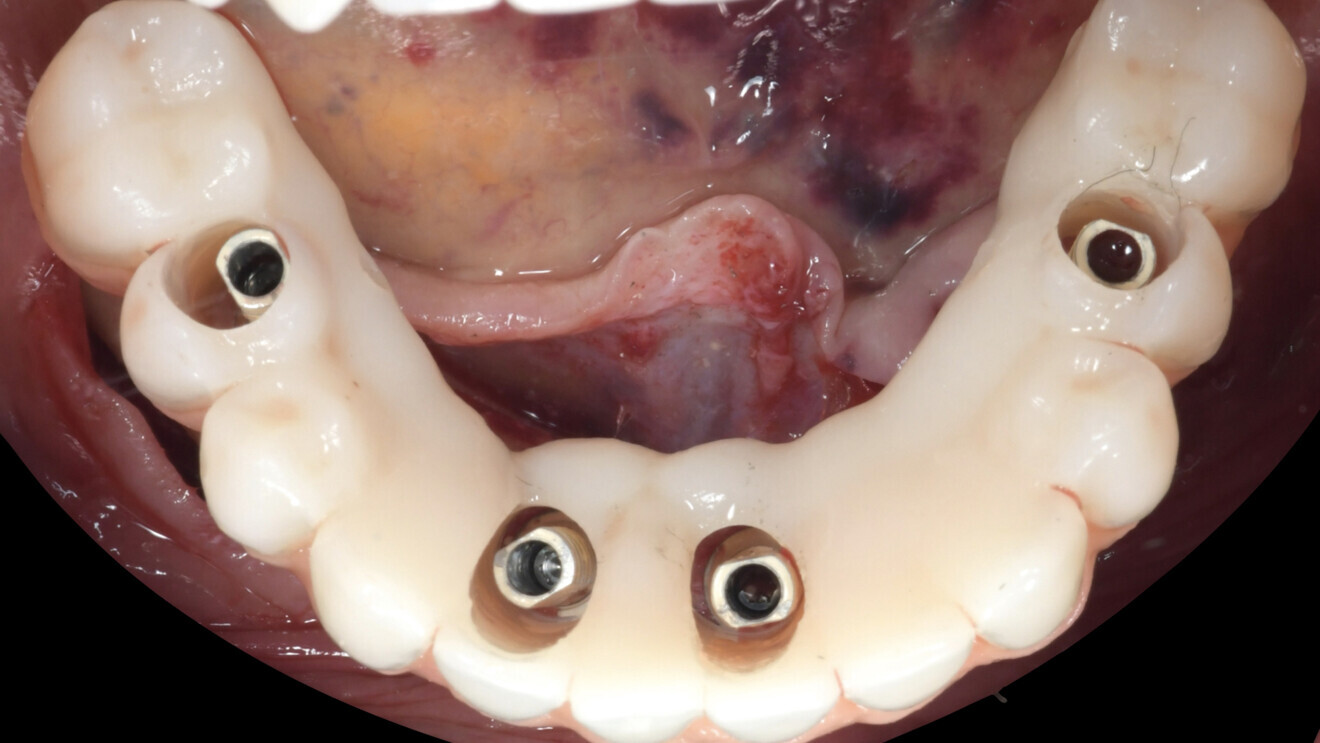

Le projet prothétique (validé préalablement en bouche) peut être aussi numérisé en fichier STP et, dès lors, il peut être combiné avec le fichier STL de la situation initiale. Cela permet de faire apparaître le projet prothétique sur les données osseuses : la planification est alors plus fonctionnelle et biologique. Dans le même temps, il est possible de transformer ce projet prothétique en prothèse provisoire (logiciel DTX Lab) adapté à la planification (perforation de la prothèse en regard de la position des futurs implants et piliers). Cette prothèse comporte également quatre tiges au niveau de l’intrados, dessinées en regard de zones osseuses. Après forage guidé par la navigation, elles permettent de positionner la prothèse correctement (Fig. 7). La prothèse provisoire a été préparée en PMMA et réalisée avec une résine composite rose pour simuler la gencive (Fig. 8).

Il est décidé d’utiliser des implants N1 (Nobel Biocare ; Fig. 10). Les piliers prothétiques sont mis en place et vissés au couple de serrage préconisé, et les piliers provisoires en titane ont été vissés sur les piliers prothétiques (Fig. 11).

La prothèse provisoire est présentée en face des piliers provisoires puis elle est positionnée précisément grâce aux tiges qui seront réceptionnées par les logements intra-osseux réalisés par la navigation, assurant donc leur précision de positionnement. Il est alors possible d’injecter le composite Flow pour joindre les piliers provisoires et la prothèse provisoire (Fig. 12). Après adjonction et finition du composite injecté par polissage, la prothèse provisoire peut être vissée pour toute la durée de la phase d’ostéo-intégration (Fig. 13). Une radiographie réalisée après la mise en place de la prothèse provisoire a montré une bonne intégration des implants (Fig. 14).